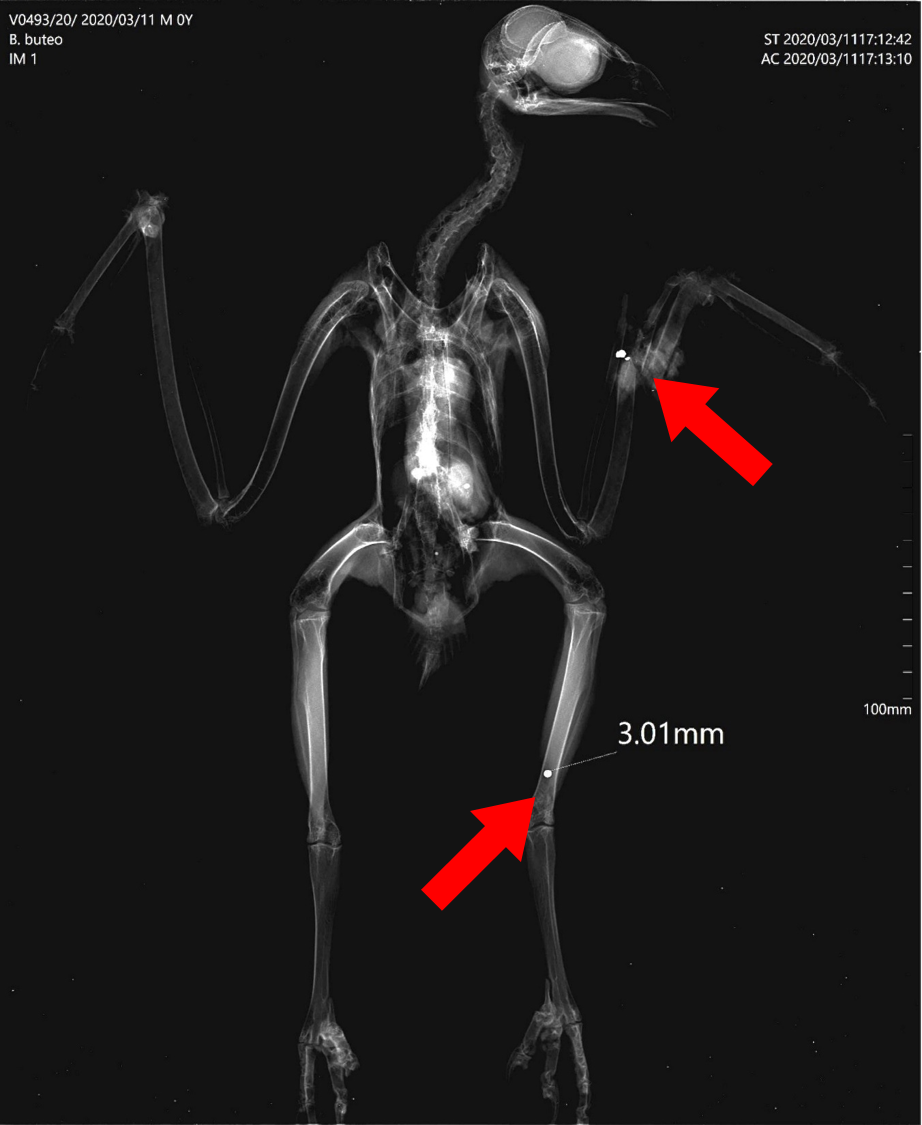

Por ter sido encontrada junto a uma estrada, suspeitava-se que pudesse ter sido atropelada. No entanto, durante a realização do exame físico, foi visível uma fratura exposta na asa esquerda que, feito o Raio-X, confirmou ser resultante de tiro. Para além disto, foi ainda visível outro projétil na pata esquerda.

Infelizmente, devido aos graves ferimentos, esta fantástica ave de rapina não sobreviveu.